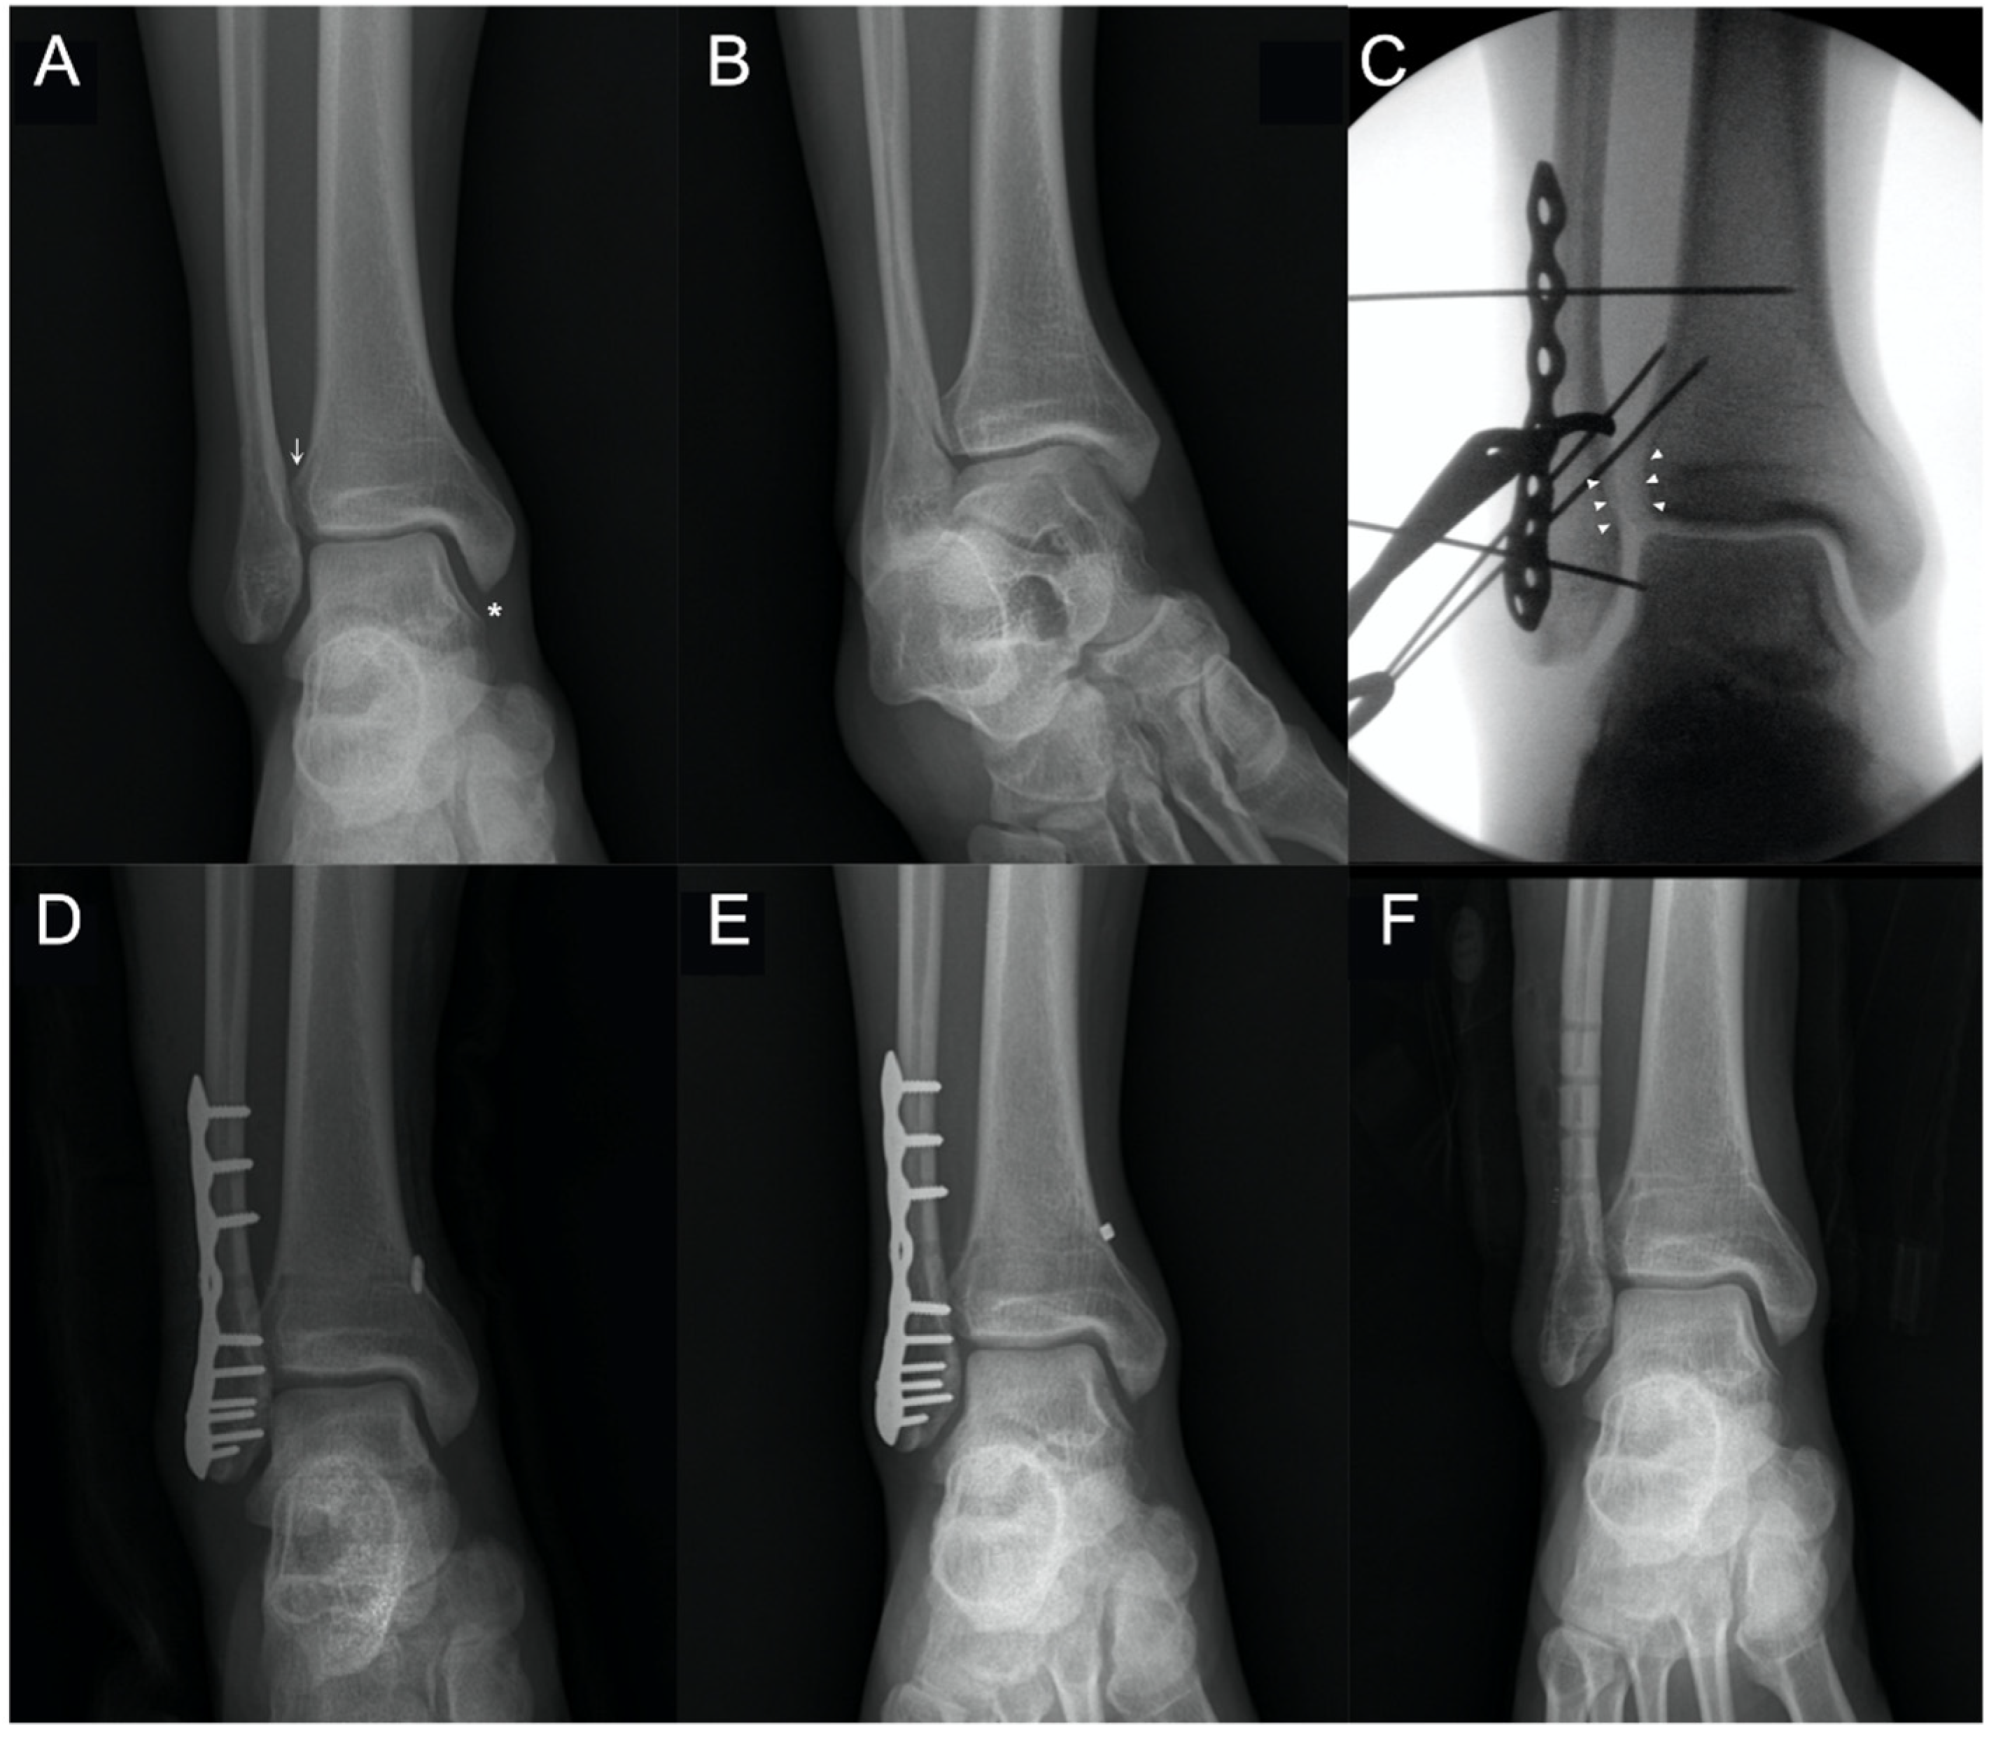

2.2. Surgical Technique

2.4. Removal of Suture Button